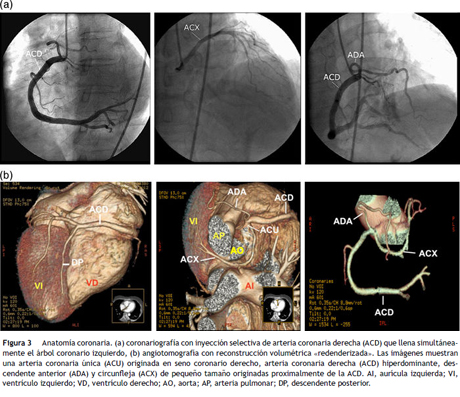

Mujer de 60 años de edad, con antecedentes de: hipertensión arterial controlada con 50 mg/día de losartan y episodios esporádicos de migraña clásica desde la juventud. Consulta al servicio de urgencias por un episodio de migraña que fue manejado con 100 mg de tramadol intramuscular, con mejoría parcial. Fue dada de alta, regresando dos horas más tarde por incremento en la intensidad de la migraña e inicio de dolor opresivo medioesternal de intensidad moderada, en los últimos veinte minutos. Al reingreso tenía: la presión arterial 150/90 mmHg, el pulso 95/min, la frecuencia respiratoria 18/min, la saturación periférica de oxígeno 98% respirando aire ambiente; sin hallazgos anormales al examen físico. El electrocardiograma (fig. 1), mostró elevación del segmento ST en V2 y V3 y la ecocardiografía (fig. 2a), acinesia de los segmentos apicales y medios de las diferentes paredes del ventrículo izquierdo con «balonamiento apical» y una fracción de eyección del 27% por el método de Simpson modificado; hallazgos que conducen a plantear un diagnóstico presuntivo de la miocardiopatía de takotsubo. Treinta minutos posteriores al ingreso, se le realizó un cateterismo cardiaco (fig. 3a), encontrándose una arteria coronaria única que se originaba en el ostium coronario derecho, sin encontrarse lesiones angiográficas o vasoespasmo. La arteria coronaria única derecha era hiperdominante, bordeaba el surco auriculoventricular posterior. El árbol coronario izquierdo estaba poco desarrollado con ausencia del tronco coronario común izquierdo. La coronaria descendente anterior y la circunfleja, tenían orígenes independientes en la coronaria derecha proximal. La arteria descendente anterior, seguía un trayecto anterior hacia la izquierda sobre el tracto de salida del ventrículo derecho alcanzando el surco interventricular anterior. La arteria circunfleja, de mayor longitud que la arteria descendente anterior, seguía un trayecto posterior hacia la izquierda, entre los grandes vasos y la aurícula izquierda. Durante la realización de la coronariografía, el dolor torácico desapareció espontáneamente sin reaparecer posteriormente. La paciente fue manejada con enoxaparina a dosis de anticoagulación, ácido acetil salicílico, carvedilol, enalapril y atorvastatina. La troponina T obtenida a las 12 horas del ingreso fue de 0.566 ng/ml (vn 0-0.014), con control de 0.377 ng/ml 24 horas después del ingreso, con la creatinfosfoquinasa total de 246 U/L (vn 0-190) y MB de 39.8 (vn 0-24), TSH 1.41 uUL (vn 0.27-4.2), el sodio 145 mmol/lt (vn 135-149), el potasio 4.1 mmol/lt (vn 3.5-5.1) y la creatinina sérica de 0.66 mg/lt. Diez días más tarde, la paciente fue dada de alta con el tratamiento que venía recibiendo y la anticoagulación con la warfarina. Como estudios adicionales, se realizaron: una tomografía computarizada simple del cráneo, que fue normal y una angiotomografía coronaria multicorte (fig. 3b) que confirmó los hallazgos de la coronariografía, excluyendo el trayecto interarterial de algún brazo coronario mayor. El electrocardiograma (fig. 1) y la ecocardiografía de control (fig. 2b) realizados dos meses más tarde, fueron normales. Un estudio de perfusión miocárdica de estrés con ejercicio realizado a los 30 días, fue normal. Teniendo en cuenta la edad, la ausencia de síntomas previos atribuibles a la isquemia miocárdica, la perfusión miocárdica normal y la ausencia de lesiones coronarias o el trayecto interarterial de un brazo mayor; no se consideró algún procedimiento de la revascularización. Transcurridos 12 meses posteriores al evento agudo, la paciente ha permanecido asintomática con manejo farmacológico.

Inicialmente, en este caso, al encontrarse una arteria coronaria única en la coronariografía, se planteó la posibilidad de un recorrido entre la aorta y la pulmonar de algún brazo coronario mayor como causa de la isquemia miocárdica, sospecha que fue descartada posteriormente mediante la angiotomografía coronaria multicorte. La anatomía de la arteria coronaria única en este caso, corresponde a un tipo angiográfico R-IIIC según la clasificación de Lipton modificada10. Neil y colaboradores en el año 200011, informan sobre un caso de la arteria coronaria única con anatomía angiográfica similar a la descrita, la cual según los autores, no había sido reportada en la literatura y hasta la actualidad no se encuentran otros reportes similares. Este hallazgo aporta un elemento adicional de originalidad al caso presentado, especialmente, si consideramos que después de una búsqueda bibliográfica exhaustiva en las bases de datos de: Medline, Scopus, Scielo, Lilacs e Imbiomed, utilizando palabras clave relacionadas con ambas entidades, no se encontró ningún caso informado que hiciera referencia a la coexistencia de la miocardiopatía de takotsubo y la arteria coronaria única, siendo el caso presentado el primero en publicarse que informa dicha coincidencia diagnóstica.